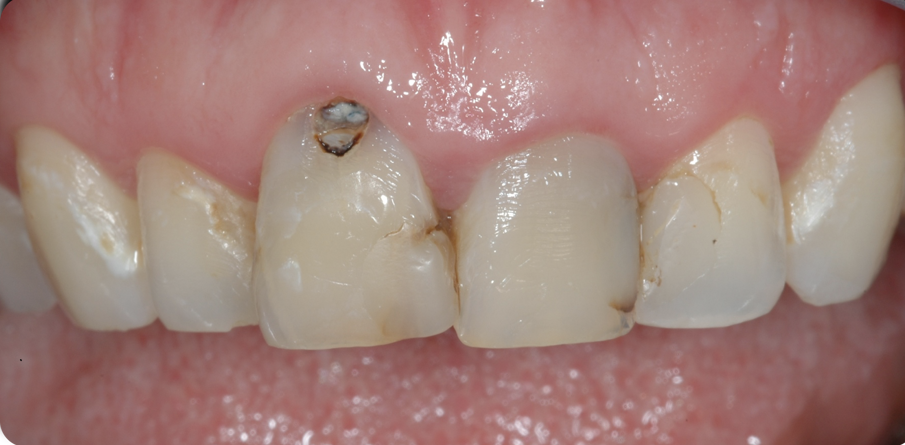

Una giovane paziente di 31 anni, si presenta al mio studio per risolvere l’inestetismo provocato dalla presenza di carie al colletto dell’11, e asimmerie delle parabole. Gli elementi frontali dal 12 al 22 presentavano inoltre diverse carie della corona clinica e contestualmente delle radici trattate in modo incongruo, tanto da provocare delle lesioni endodontiche molto ampie.

Figg. 1, 2 - Situazione iniziale.